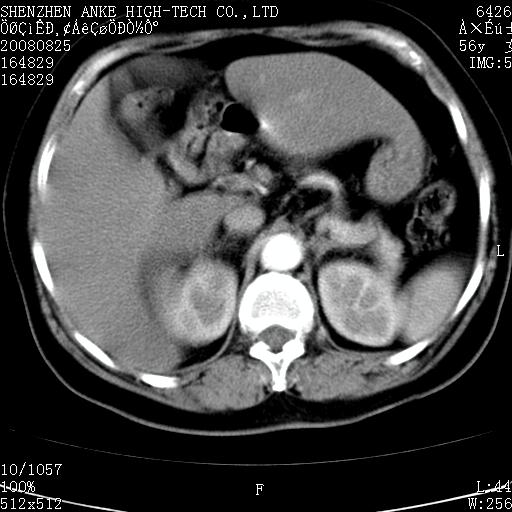

患者,女性,56岁,腰痛3年,查:右腹部约8x10cm肿块,固定,无压痛;8月23日在外院做了平扫,发现右肾巨大肿块(外院具体诊断不祥);今天在我院做了静脉肾盂造影,示:右肾明显增大,分泌功能明显减弱。

右肾癌可能大。

右肾癌

支持右巨大肾癌。

1)考虑右肾癌并右肾静脉瘤栓形成。2)脂肪肝。